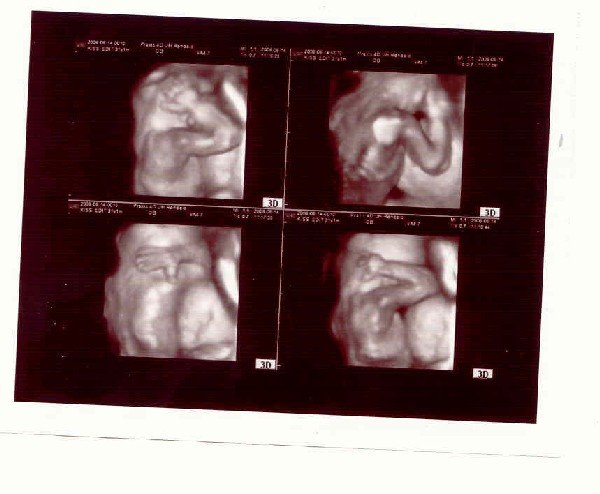

szuper hogy a 4D-n mar nem latszot a szalag

Mi s Gyorfinel voltunk anno,O a z orszag egyik legjobb szonografusa.Ha O megnyugtat akkor az tuti.

Arik a kaepek,latszik hogy Andriskat hogy takarja a fuleit,nem tetszik neki a zaj..Anno neknuk is volt ilyen kep